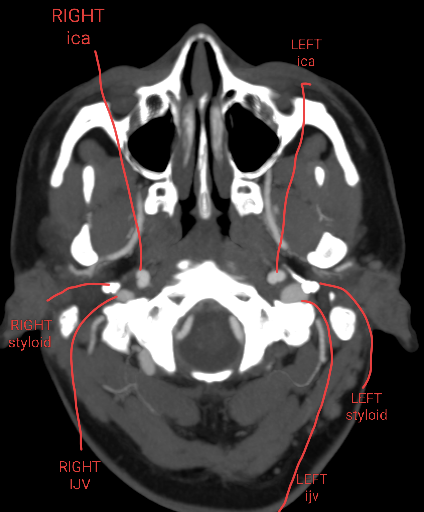

In the last image you posted there is visible compression of both your internal carotid artery & your internal jugular vein. I’ve annotated your image so you can see what is what. I may have the artery & vein mixed up but I’m pretty sure I’m correct. Your carotid is visibly narrowed immediately below your styloid then enlarges (like a small balloon) below the narrowed area. That is an indication of compression. The “ballooned” area of your carotid appears to be compressing your IJV to some extend very slightly above the transverse process of C1 which also appears to be pressing on your IJV. There is a small vein/artery (the letter F is sitting on it in your image) which runs diagonally across both the ICA & IJV, just slightly above the transverse process, which appears to possibly be contributing to compression of both the ICA & IJV. It’s marked w/ a yellow arrow in the annotation.

Since you only uploaded an image of your right side, I’m wondering if the left side might also display some interesting problems, but these can be just one sided so hopefully that’s so in your case.

I agree with everything you’ve said. Your left ijv (right side of image) is in contact with your left styloid. Once we get the full imaging we’ll probably see a greater pinch point in between the two slices you’ve sent.

I think you’re right about the ICA and it looking weird on the other slice due to it being tortuous!